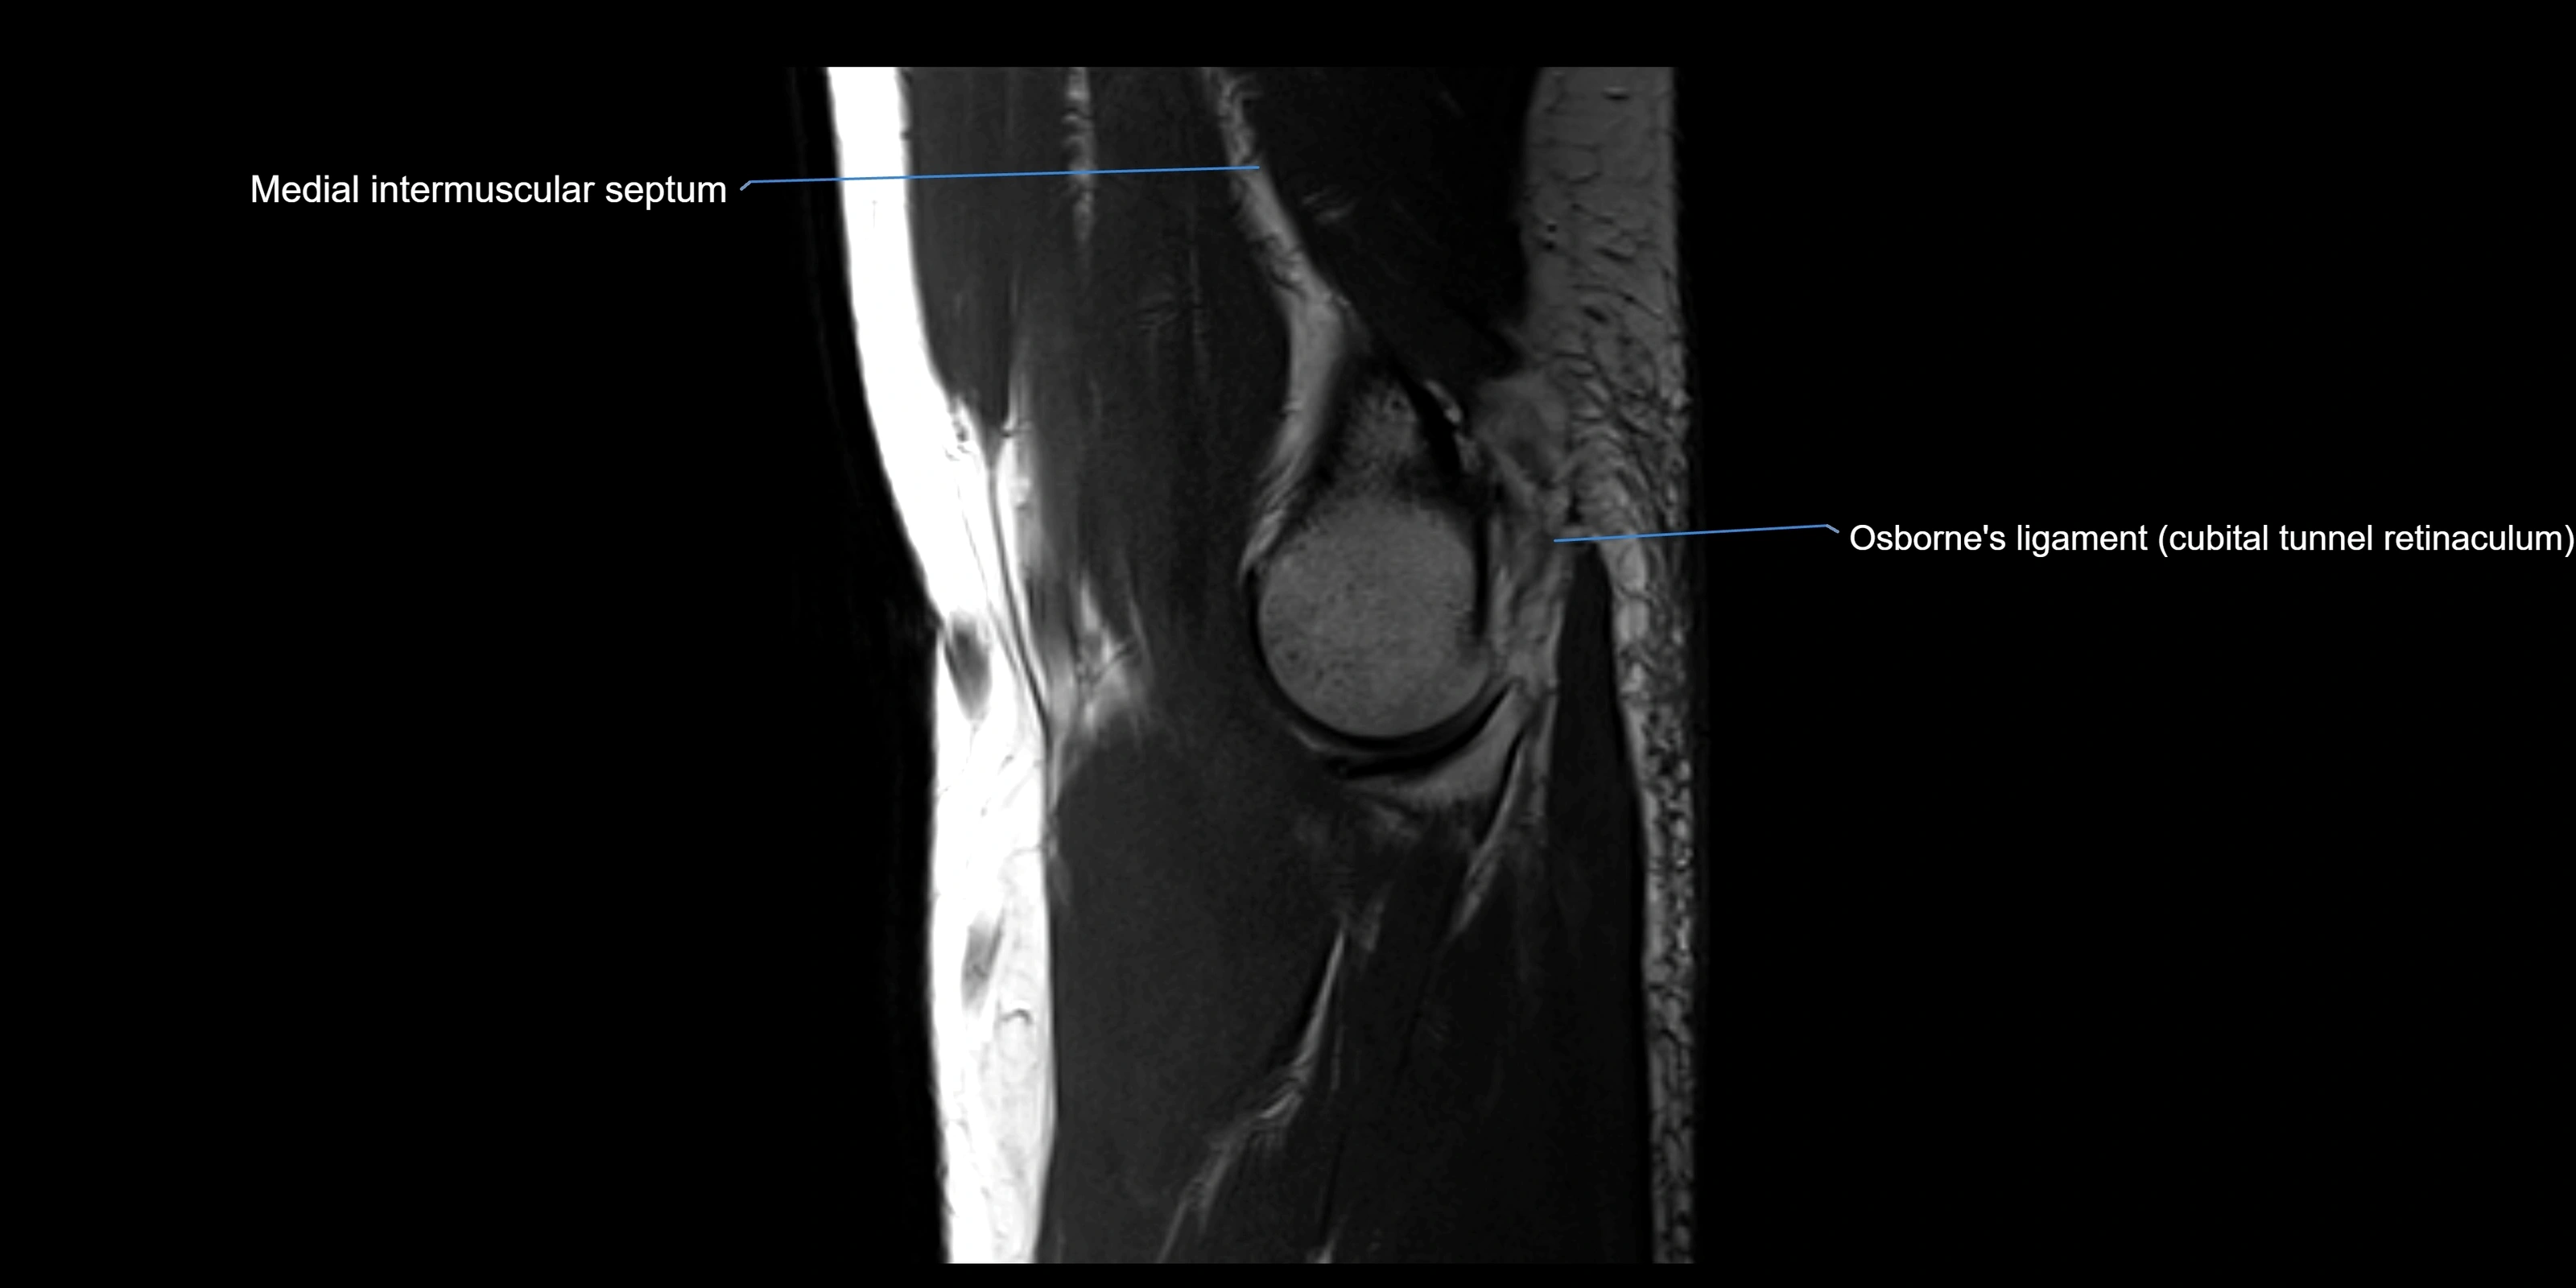

MRI images

image